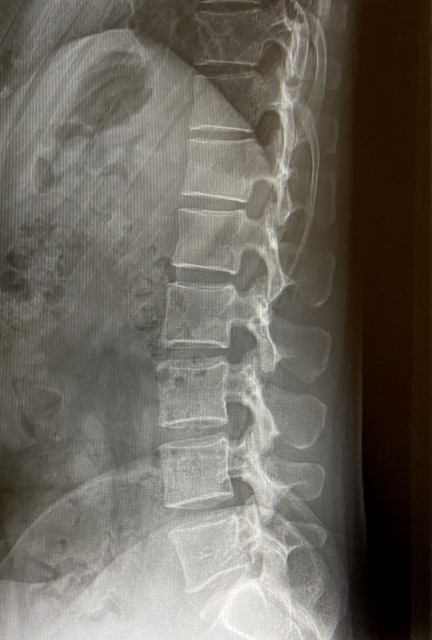

特異的腰痛とは、レントゲンやMRIなどの検査で原因が特定できるもの(腰椎椎間板ヘルニア、脊柱管狭窄症、腰椎すべり症など)

画像に写ったものが腰痛の原因とは限らない

さらに、やっかいなことに、レントゲンやMRIなど検査で、画像にヘルニア、脊柱管の狭窄、腰椎のすべりが写ったかといって、それが本当の原因とも言えないんです。

脊柱管の狭窄や腰椎のすべりなどは、老化やけがによっておこることが多いので、外科手術によって広げたりつなぎ合わせたりしなければ、大きく状態が変わることはありません。

画像には今までの結果が写っている

当院は、レントゲンやMRIには、今までその場所にどのような負担がかかってきたのかという結果が写っていると考えます。

ヘルニア、脊柱管狭窄、椎間板がつぶれるなど、画像に写る変化は、短期間でおこるものではなく長期間に渡って負担がかかることによりおこります。

ヘルニア、脊柱管狭窄、椎間板がつぶれているなどが画像に写った方は、腰により多くの負担が掛かってきたわけだから改善まで時間を要するかもしれないなと一つの参考にします。